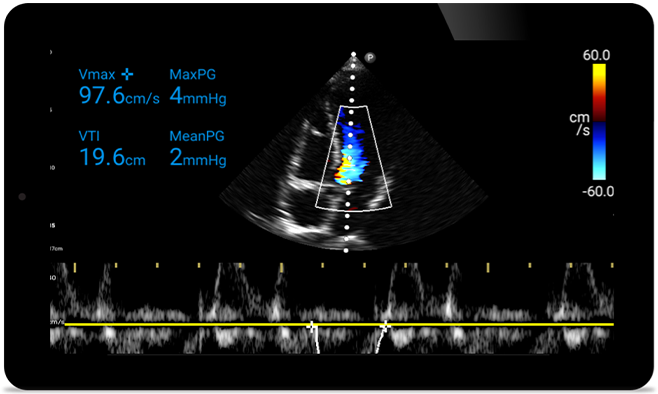

Act faster to protect their heart

Act faster to protect

their heart

When seconds count, portable ultrasound can make the difference. Lumify can provide the high-definition imagery you need whenever and wherever you need it.